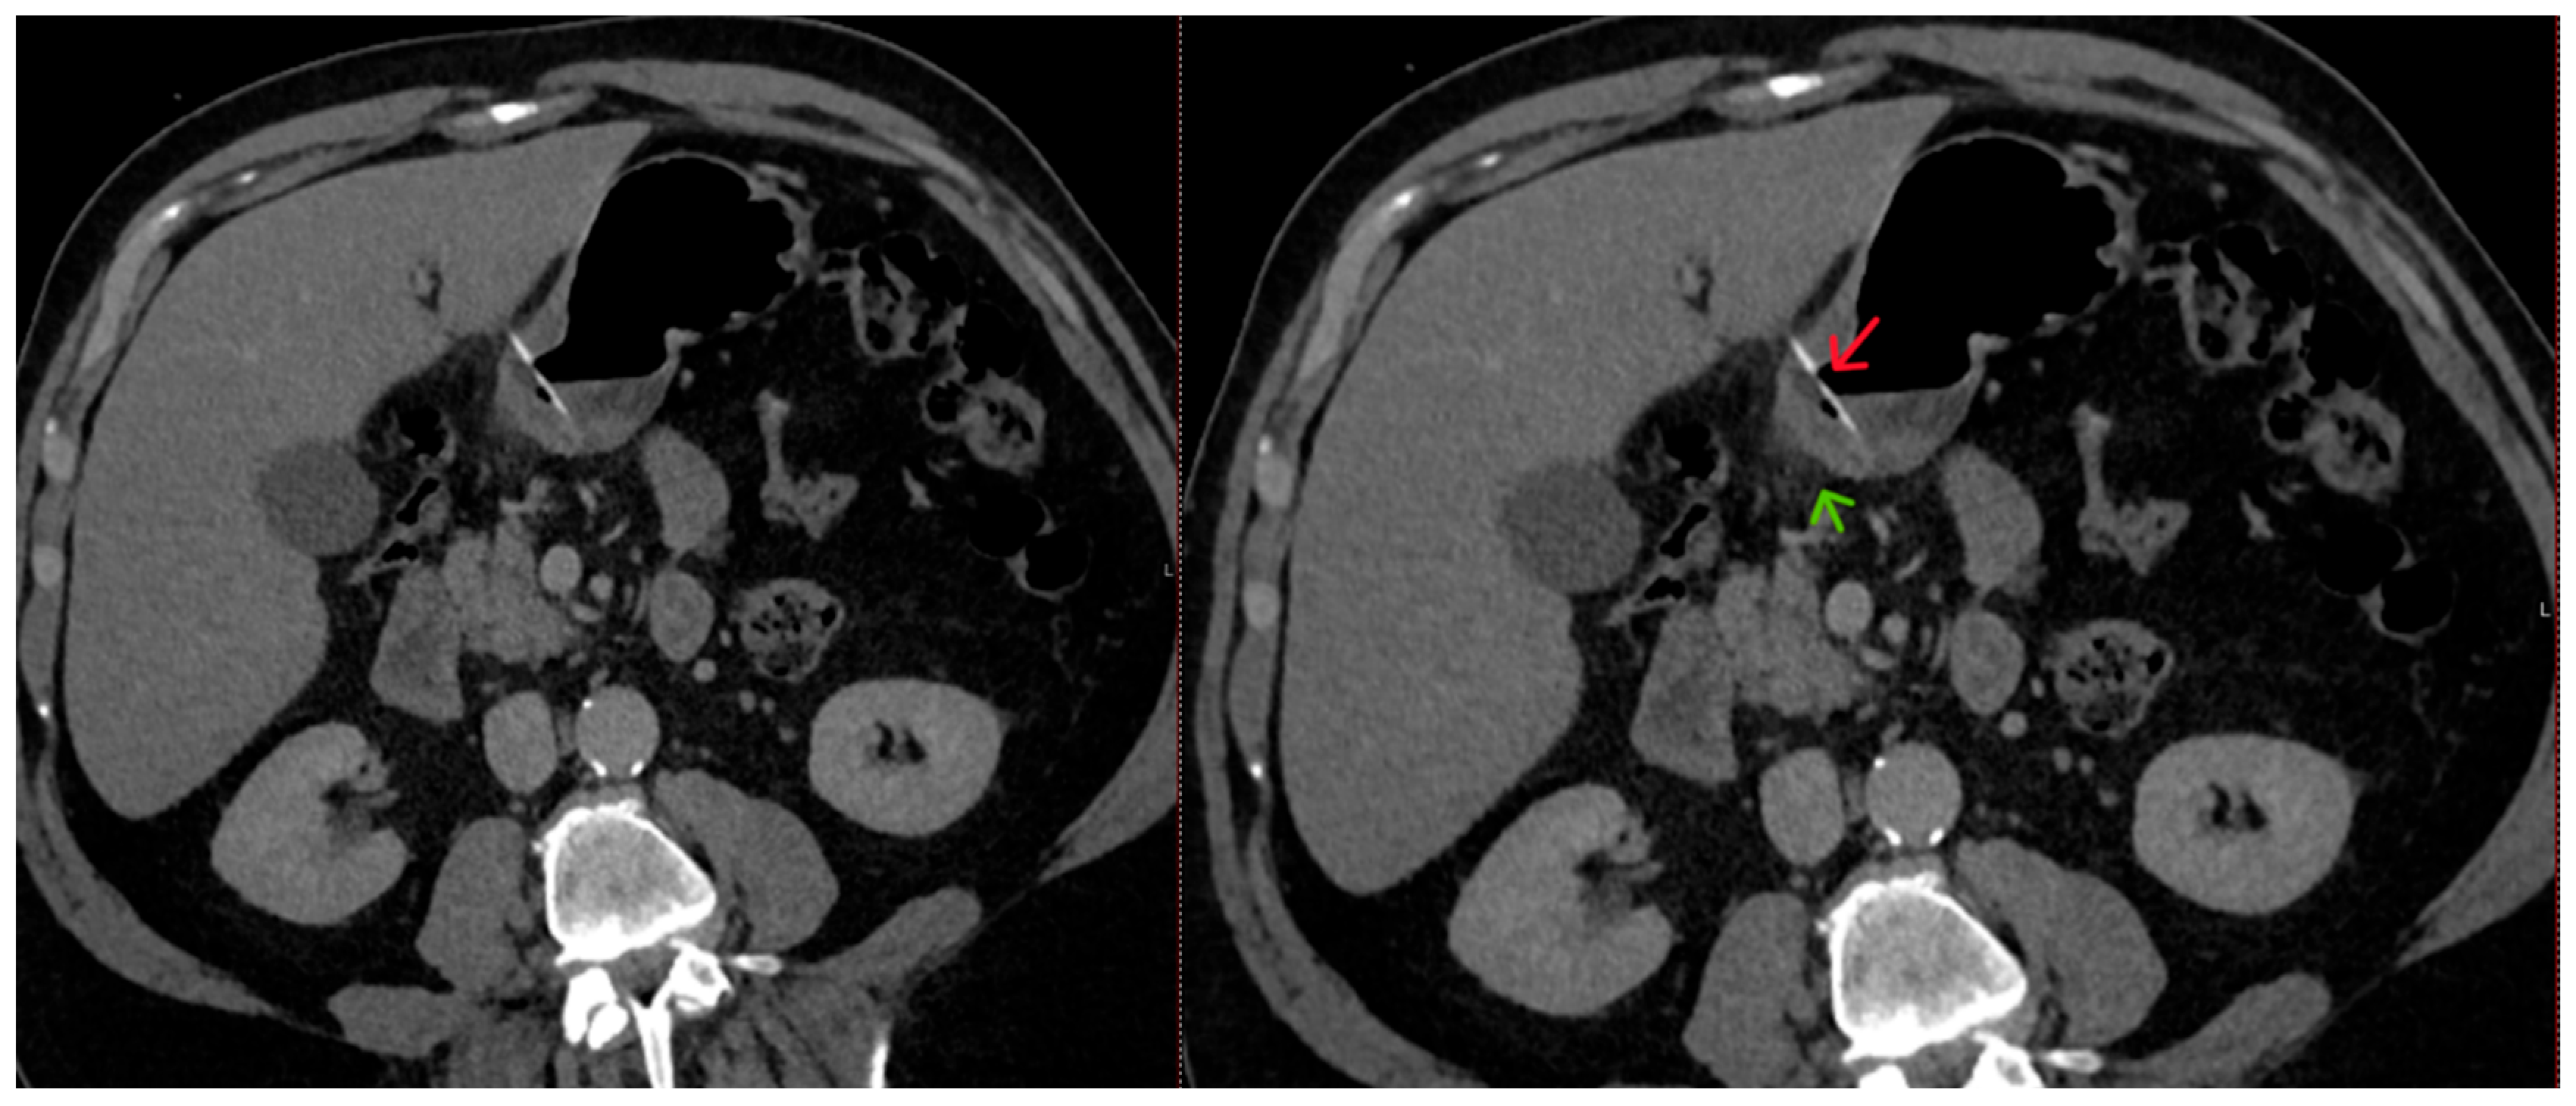

The abdominal CT scan showed a foreign body in the pylorus of the stomach that was penetrating the wall of the stomach (Figure 1). There was also air outside the stomach, along with signs of inflammation in the adjacent adipose fatty tissue (Figure 2 and Figure 3). The diagnosis of perforation of the stomach wall with a foreign body was made, leading to subsequent concealed, local peritonitis.

Figure 2. A linear foreign body is present in the stomach lumen (red arrow), perforating the gastric wall, with surrounding fat stranding (green arrow) resulting from inflammation.